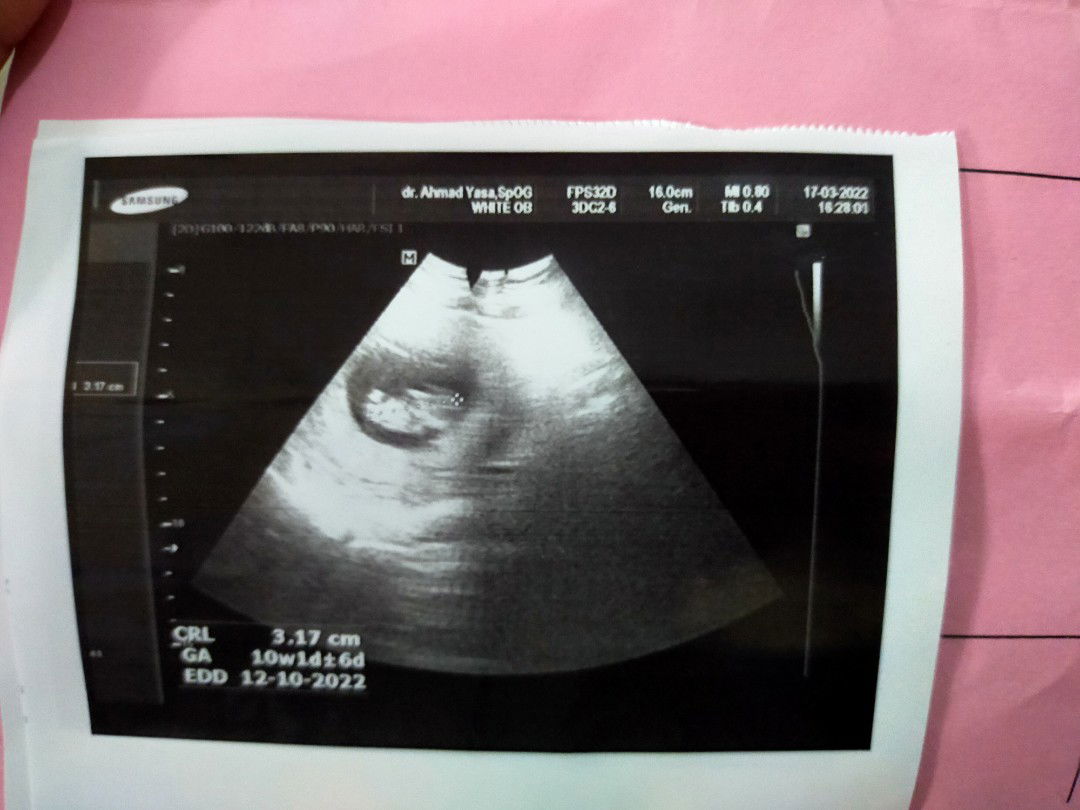

september or oktober 2022. semoga lahiran nya lancar normal sehat sehat untuk kedua nya. Aamiin yallah🤲